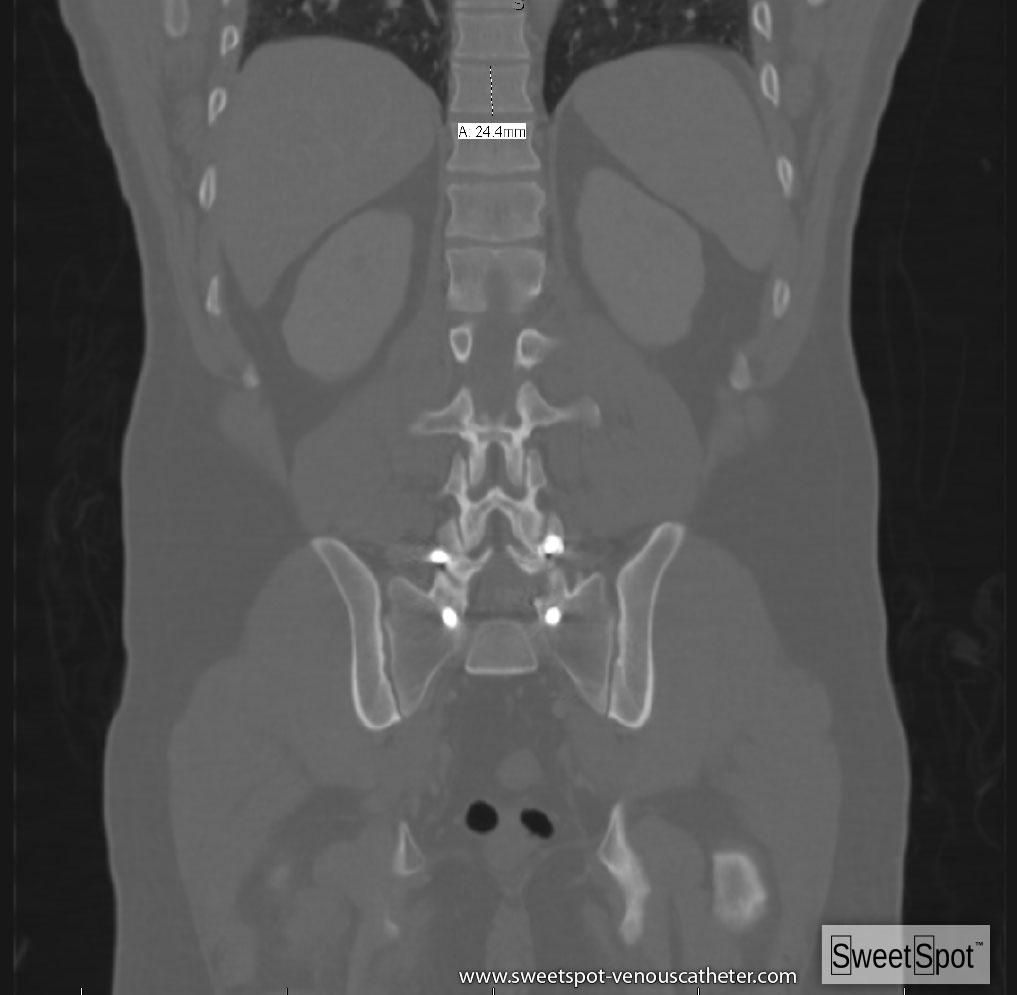

Coronal reformation CT. Example of average height of dorsal vertebral body ≈ 2.5cm "internal ruler." |